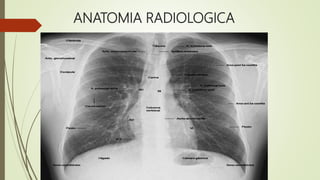

ANATOMIA RADIOLOGICA

ARBOL

TRAQUEOBRONQUIAL

• En las radiografías PA la tráquea se ve como una

radiolucencia vertical.

• El bronquio principal derecho es mucho más corto y

vertical que el izquierdo y ambos se ven bien en la PA.